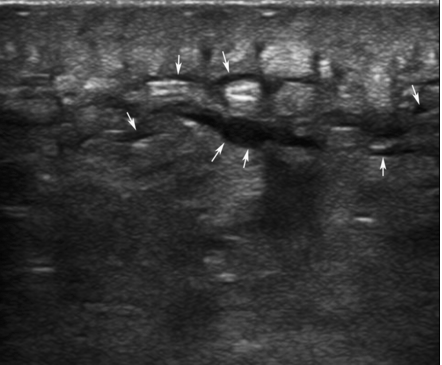

So, when you look with ultrasound, it may be tricky. Take a look at their images below: which one is cellulitis and which is an abscess? It can be tough…. they again describe the technique of compression to help you…

In that article, they state: “…studies have confirmed anecdotal clinical evidence that the physical examination is often incorrect. In fact, not only was incision and drainage being performed unnecessarily, in some cases, needed procedures were missed after failure to recognize the presence of an abscess. With the recent spread of sonography into clinical practice, multiple descriptions of point-of-care sonography use in suspected soft tissue infections have been published. Some have even noted that blind incision and drainage, once thought to be harmless, could lead to serious potential complications because not all red swollen structures should be cut with a scalpel.”